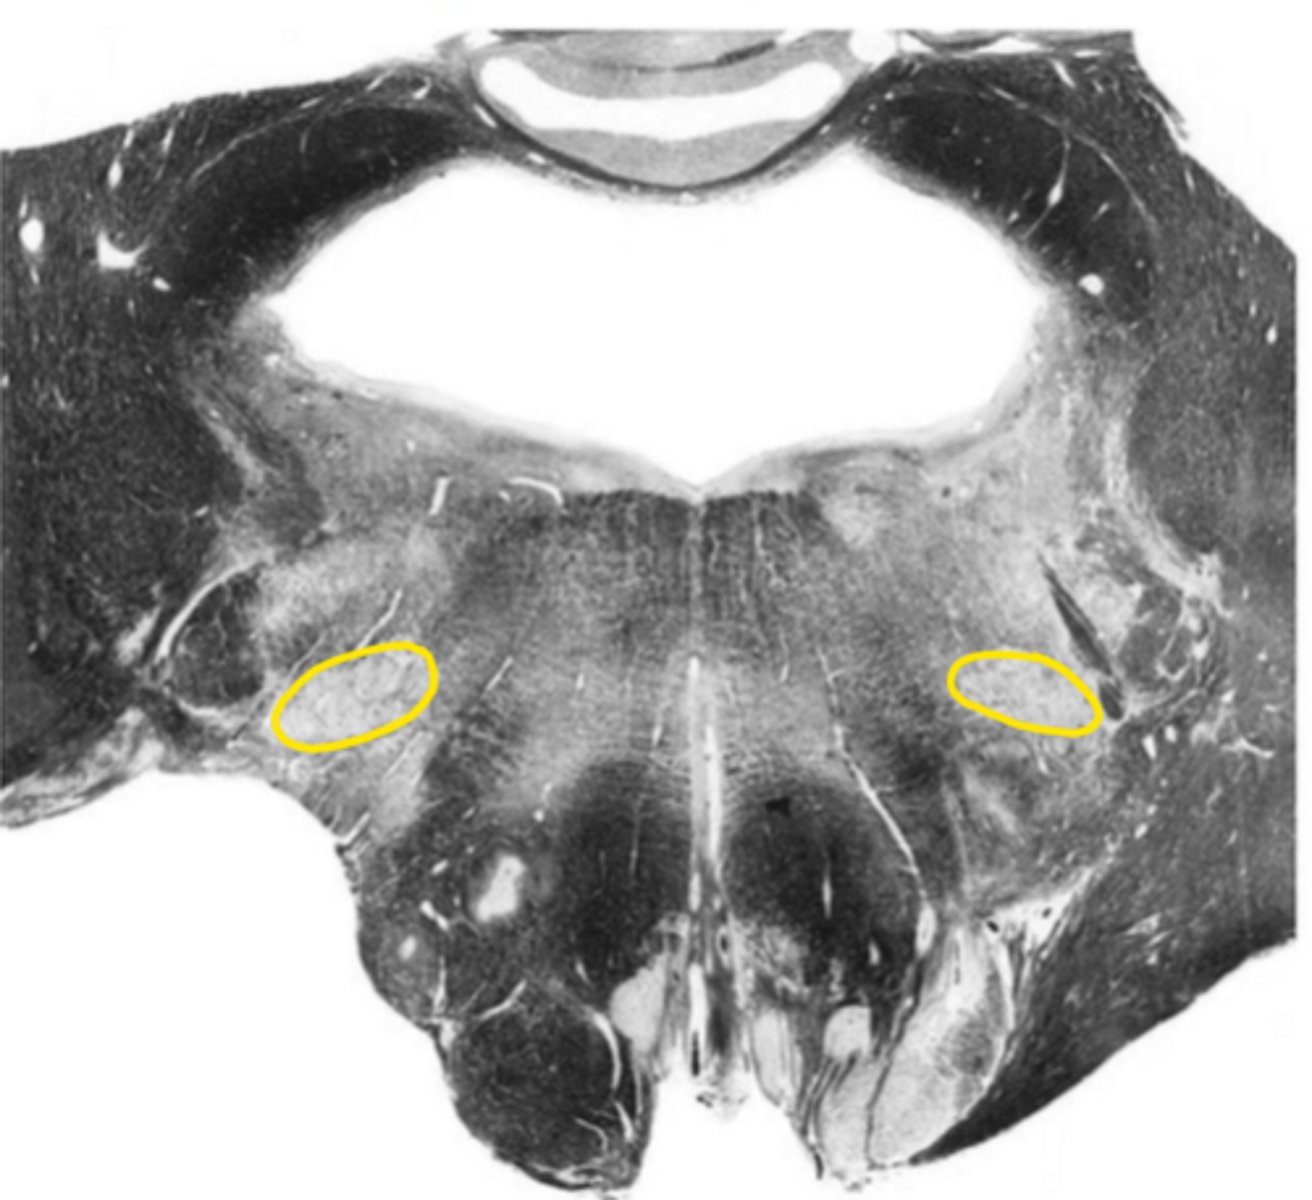

medial lemniscus

ID the structure

corticospinal fibers

pontine nucleus

ID the nucleus

vestibular nucleus

abducens nucleus

facial nucleus

facial nerve

ID the nerve

fourth ventricle

ID the space

reticular formation

inferior cerebellar peduncles

olive

principle olivary nucleus

pre-olivary sulcus

anterior median sulcus